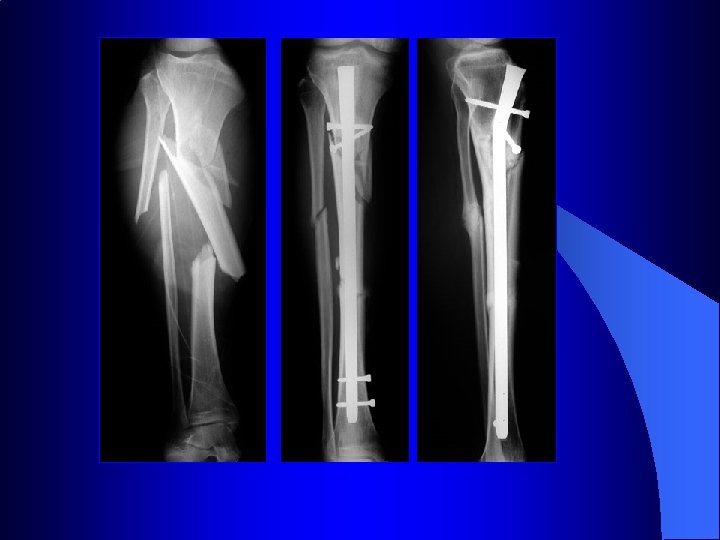

Le verrouillage est indiqué dans les fractures comminutives afin de préserver la longueur et empêcher la rotation

Le verrouillage est indiqué dans les fractures comminutives afin de préserver la longueur et empêcher la rotation Formation d’un gros cal grâce à l’hématome périfracturaire préservé